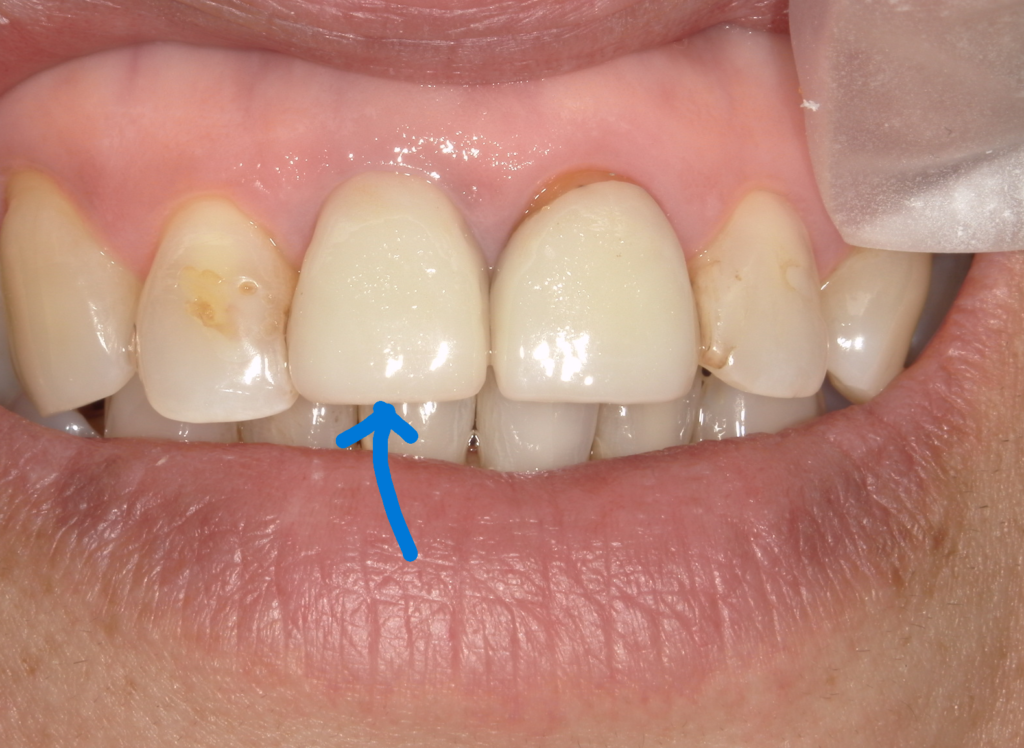

この方はインプラントを行ってから4年経っています。青い矢印がインプラント(自分の歯ではありません 骨の中に人工歯根チタン製が入っています)

ご本人は大変満足されています。

拡大してみますと、どうしても一般の方は歯の色の微妙な違いが気になるかもしれません。しかし私たちが見るところは青い〇 と緑の〇。ここら辺なのです。

根本のふくらみが自分の歯とインプラントとが何年たってもそんなに違わない。

いい状態を保っています。